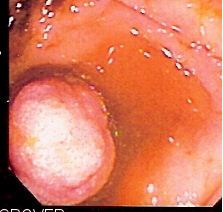

대장암 검사는 조기에 발견하면 예방이 거의 가능하다. 대장암은 대장용종이라는 양성 성장을 통해 발생하기 때문이다. 대장내시경을 통해 대장 용종을 발견하고 절제할 수 있다.[29]

대장암 검진은 충분히 일찍 실시하면 용종 단계에서 발견하여 제거할 수 있다. 암이 발생하면 결장 절제술과 같은 더 침습적인 수술이 필요하고, 암이 더 퍼지면 다른 치료 방법이 필요하다. 따라서 조기 진단은 더 침습적인 치료의 필요성을 줄여준다.[29][30]

분변 잠혈 검사법은 사망률 감소 효과가 증명되어 국가 암 검진과 선택적 암 검진 모두에서 권장된다. 대장 내시경 검사 역시 사망률 감소 효과가 증명되었지만, 무시할 수 없는 단점도 존재한다.[62]